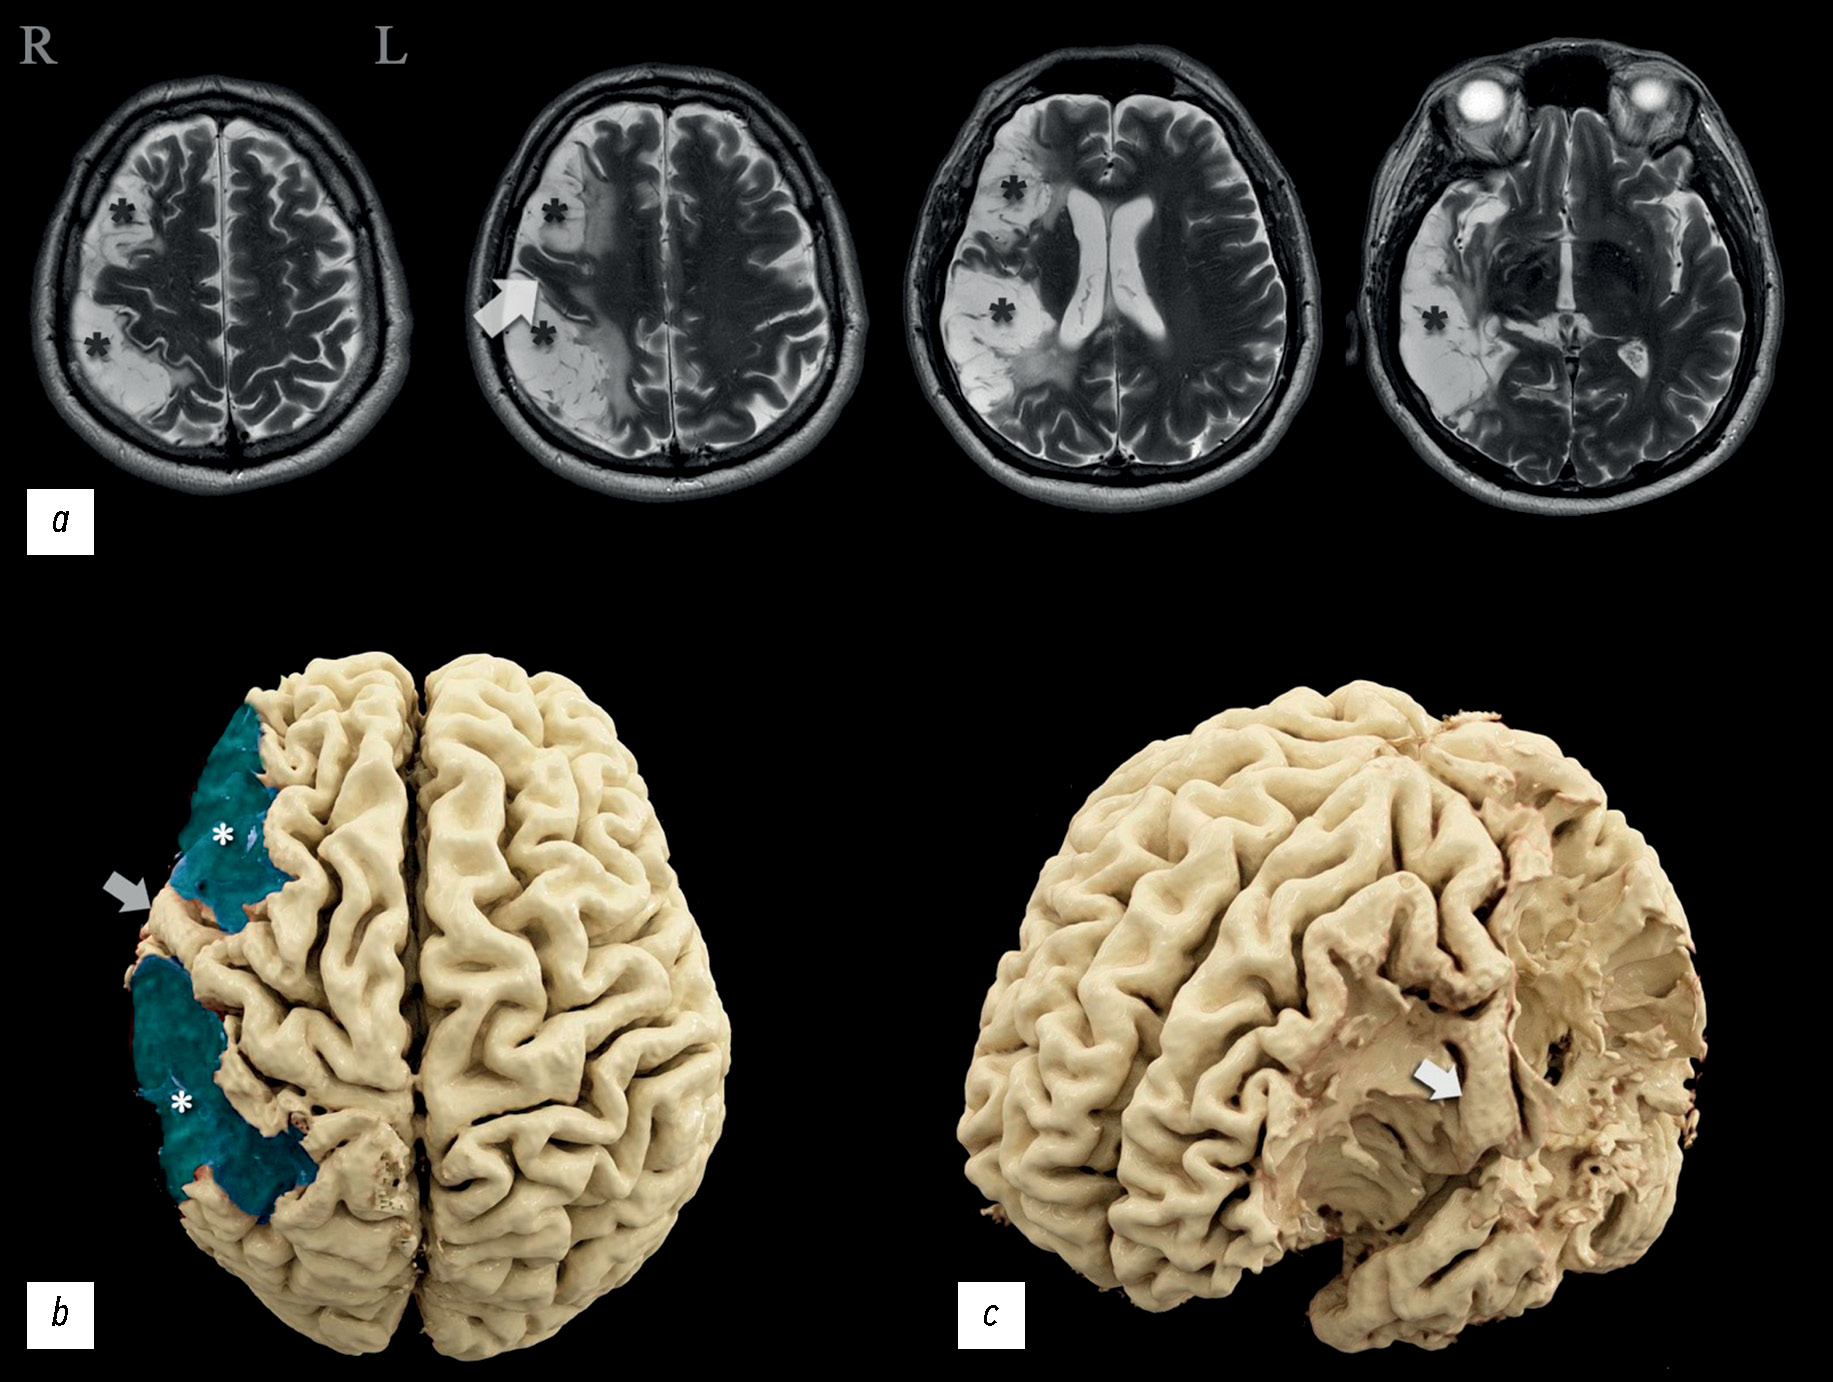

通过核磁共振纤维束成像、功能性核磁共振成像和脑电图分析中风后大脑下半球广泛损伤导致轻度神经功能缺损的临床病例。

包括大脑皮层在内的大脑不同部位受损后,神经功能缺损和生活质量下降的严重程度会有很大差异,通常与损伤量无关。病理变化的定位起着重要作用。 众所周知,优势半球和次优势半球的病变在临床表现和患者生活质量下降的程度上都有显著差异。

在临床病例分析中,一名患者在两次缺血性脑卒中后入院接受康复治疗,神经科医生和神经心理学家对其进行了检查,并通过脑电图、核磁共振成像、灌注评估计算机断层扫描、核磁共振纤维束成像和功能性核磁共振成像进行了全面的仪器检查。患者左侧肢体轻微瘫痪,自主活动调节能力障碍,神经动态指数轻度下降,注意力轻度下降,对自己的病情持批评态度。神经影像学检查结果发现,大脑中动脉区域的右侧次优势大脑半球存在广泛的梗塞后损伤。

显示脑损伤量与临床表现严重程度之间的失衡,并分析造成失衡的可能原因。根据功能研究的数据,确定优势半球,并提出功能中心重组的可能变体。与类似临床病例进行比较,分析其与本文的关系。所获得的信息扩展着运动执行、语言功能和运算能力主题改变区的认识。